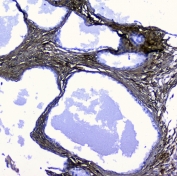

IHC staining of FFPE human ovarian cancer with LUM antibody at 1ug/ml. HIER: boil tissue sections in pH6, 10mM citrate buffer, for 10-20 min followed by cooling at RT for 20 min.